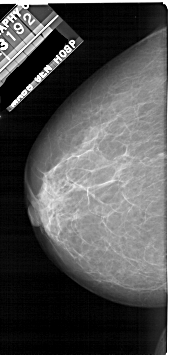

A_1922_1.RIGHT_CC

RIGHT_CC LINES 4981 PIXELS_PER_LINE 2371 BITS_PER_PIXEL 12 RESOLUTION 43.5 OVERLAY